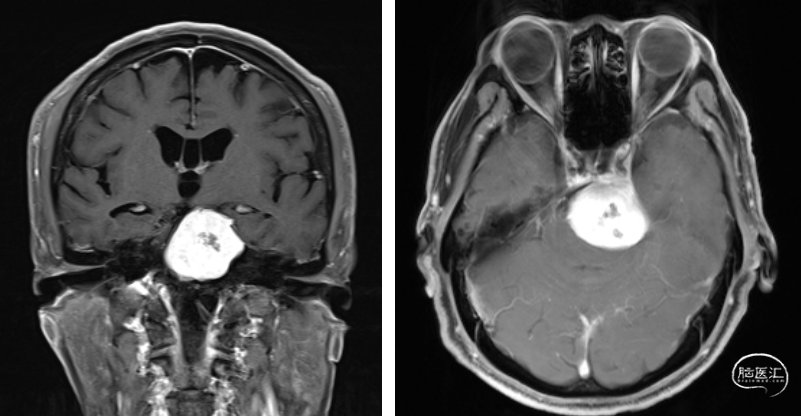

术前检查

术前诊断

手术策略